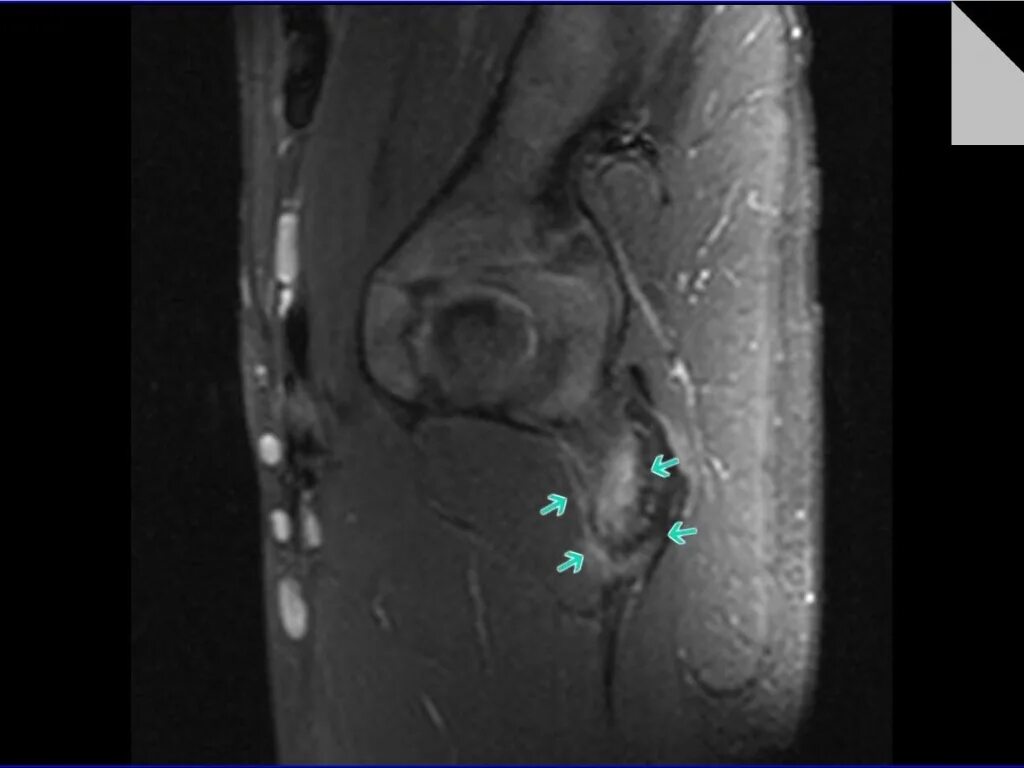

Хамстринг синдром тазобедренного сустава